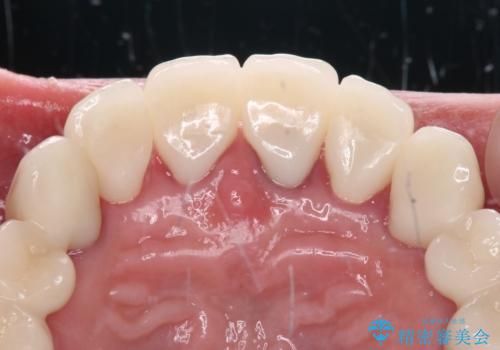

歯肉の状態が落ち着いた後に下顎の矯正治療を行い、その後補綴治療を行うこととしました。

油断をするとすぐに汚れが溜まって歯肉が腫れてきてしまうため、今後も定期的なメインテナンスが重要となります。